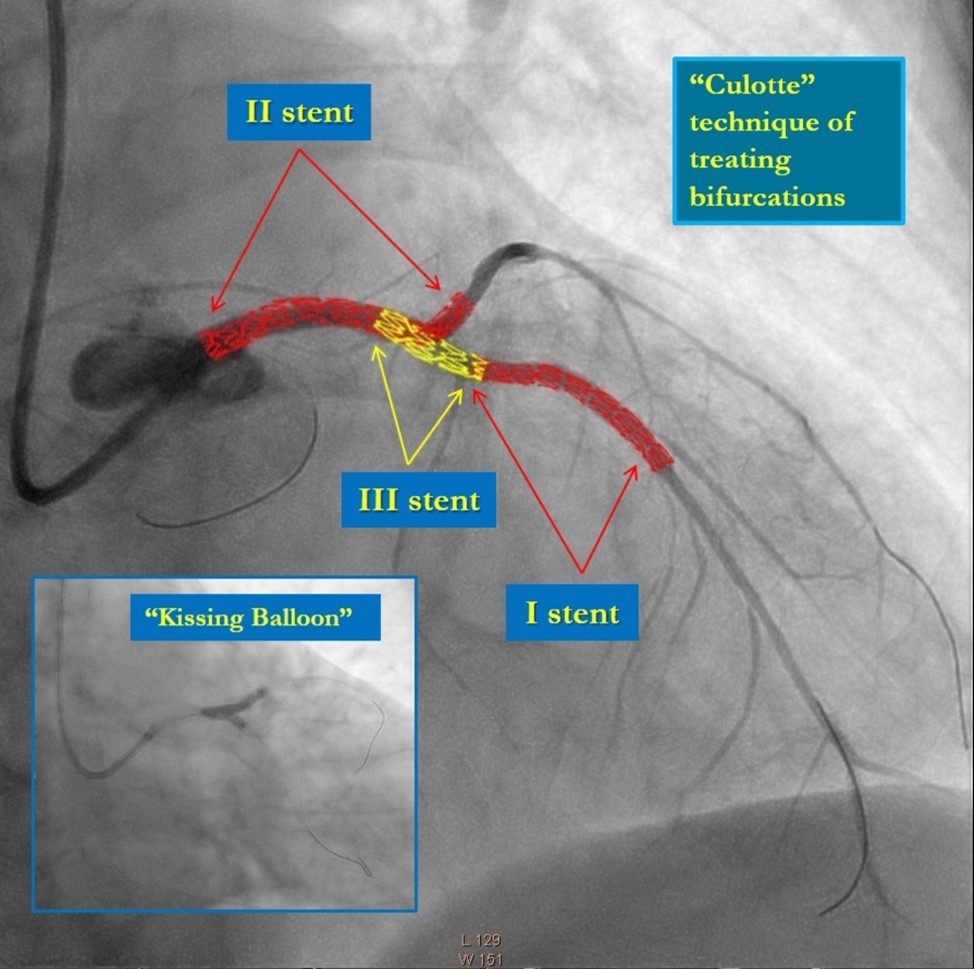

Recanalization of the occluded LMCA and LAD was performed by utilizing the support-balloon technique, and CTO wires (Miracle 3™ wire, Abbott Vascular; Runthrough® NS Intermediate wire, Terumo); LAD, CX, LMCA, and its bifurcation, were stented with 3 drug-eluting stents (Resolute Integrity DES, Medtronic); the "Culotte Stenting " technique was used for bifurcation stenting, followed by "Kissing Balloon" post-dilatation technique; proximal optimization technique was performed in the LMCA.

Recanalization

Recanalization of the occluded LMCA and LAD was performed by utilizing the support-balloon technique, and CTO wires (Miracle 3™ wire, Abbott Vascular; Runthrough® NS Intermediate wire, Terumo); LAD, CX, LMCA, and its bifurcation, were stented with 3 drug-eluting stents (Resolute Integrity DES, Medtronic); the "Culotte Stenting" technique was used for bifurcation stenting, followed by "Kissing Balloon" post-dilatation technique; proximal optimization technique was performed in the LMCA.

In the first stage, occluded left main and circumflex arteries were recanalized utilizing the support-balloon technique, and CTO wires (Miracle 3™ wire, Abbott Vascular; Runthrough® NS Intermediate wire, Terumo) and balloon pre dilatation was done (Figure 3). In the second stage, the occluded LAD artery was successfully recanalized by utilizing the support-balloon technique, and CTO wires (Figure 3) (due to severe calcinosis the second stage lasted 40 min). In the third stage, LAD artery, CX artery, as well as LMCA and its bifurcation, were stented with 3 drug-eluting stents (Resolute Integrity Zotarolimus DES, Medtronic), the "Culotte Stenting " technique was used for bifurcation stenting (Figure 4), followed by "Kissing Balloon" post-dilatation technique, and finally, proximal optimization technique was performed in the LMCA. The final angiographic image is good, the intervention ended without complications (Figure 5).

Figure 4.Culotte stenting technique